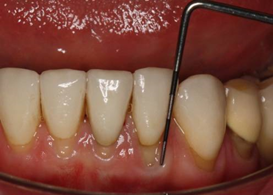

It can be difficult to accurately measure the position of the gingival margin in relation to the cementoenamel junction (CEJ) when the CEJ is not exposed. When measuring gingival recession (see figure: Measurement of recession), it is acceptable to record one measure of the greatest extent of gingival recession for both the buccal and lingual surfaces of the tooth.

The markings on the PCP 12 probe show that the recession is 2.5 mm.